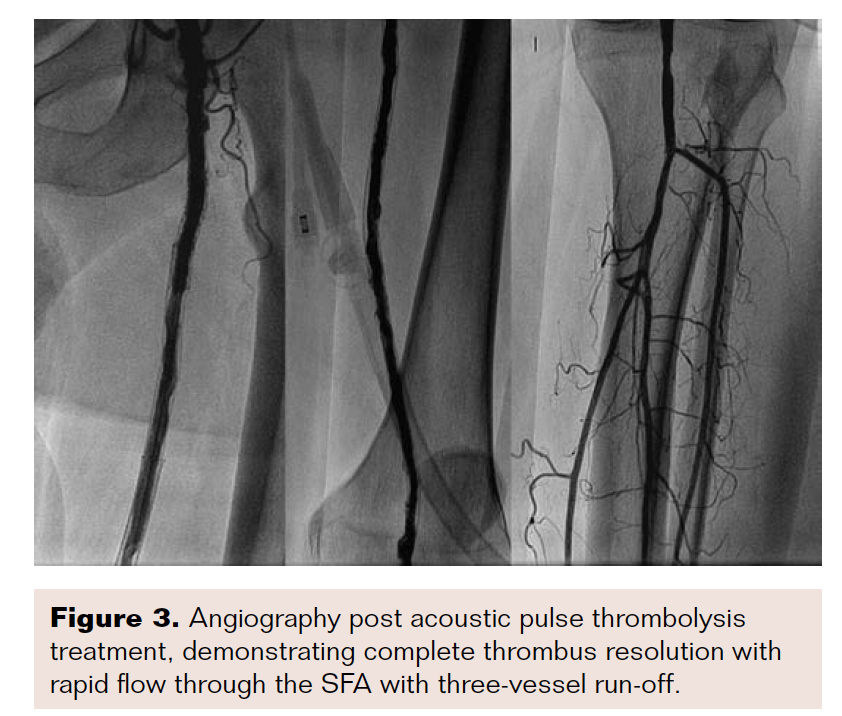

The patient underwent APT for a duration of three hours. At this time, he reported feeling significantly less pain, and a pulse was palpable in the dorsalis pedis. The Ekos catheter was removed and angiography revealed complete resolution of thrombus, with brisk inflow and outflow (Figure 3). Intravascular ultrasound demonstrated a large area of plaque burden at the distal common femoral and superficial artery junction.